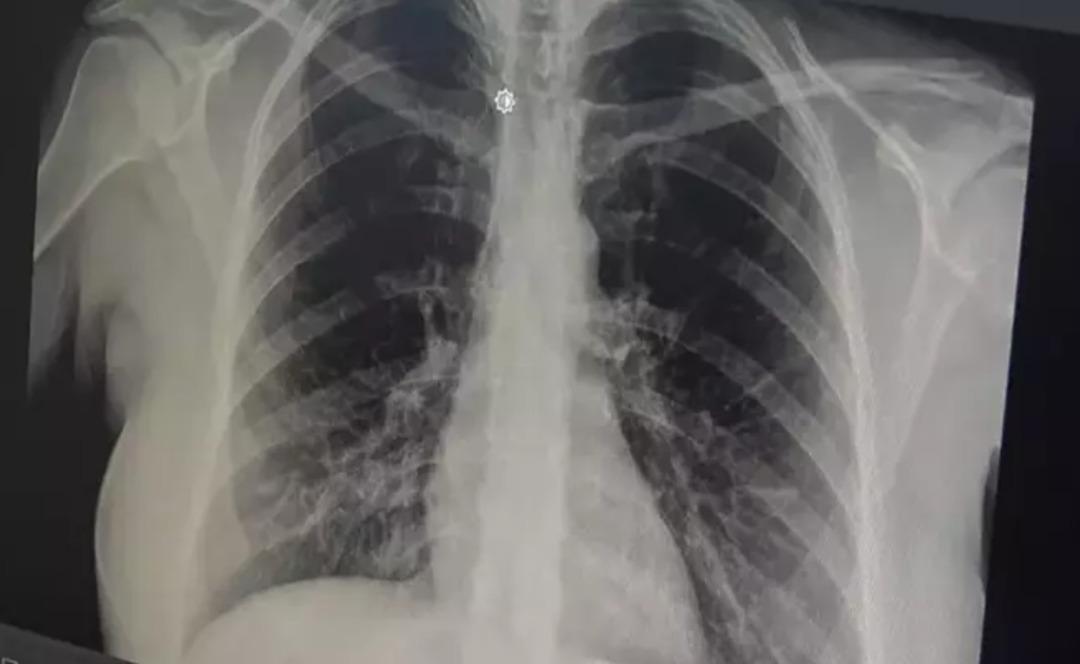

prof. Akut bronşitin solunum yolu virüslerinin neden olduğu bir hastalık olduğunu belirten Dr. Özlü, şöyle konuştu: “Günümüzde çok sık gördüğümüz bir hastalık. Genelde hastalar şöyle tarif ediyor: 'Öncelikle boğazım ağrıyordu, boğazım ağrıyordu. hafif ateş, burun akıntısı, hapşırma, geniz akıntısı ve öksürük “2-3 gündür göğsümdeydi. Nefes alırken acı hissediyorum. Göğsünde bir çalı varmış gibi geliyor ve. Nefes aldığımda oraya sıkışıp kalıyor.” Enfeksiyonun göğse kadar indiğini iddia ediyorlar. Bu doğrudur çünkü akut bronşit, solunum yolu virüslerinin neden olduğu bulaşıcı bir hastalıktır. Bu enfeksiyon üst solunum yollarıyla sınırlı olmayıp aynı zamanda alt solunum yollarımız ve bronşlarımız.

Akut bronşitin en önemli belirtisinin öksürük olduğunu vurgulayan Prof. Dr. Tevfik Özlü, “Kuru öksürük veya balgamlı öksürük şeklinde kendini gösterebiliyor. Bazen belirti daha çok hırıltılı solunum ve nefes darlığı şeklinde hissedilebiliyor. Yüksek ateş genellikle herhangi bir rahatsızlığa neden olmaz ancak bazen bakteriyel enfeksiyonlar da ortaya çıkabilir” dedi.

Bronşitin genel olarak hafif seyreden bir hastalık olduğunu ancak belirtilerin artması durumunda mutlaka doktora başvurulması gerektiğini belirten Özlü, şöyle konuştu: “Altta yatan kronik bir hastalık, astım veya kronik obstrüktif KOAH gibi bir akciğer hastalığı varsa, bronşitin akut alevlenmesidir. Buna kronik hastalık da eşlik edebilir ve genel olarak akut bronşit, nefes darlığı, hırıltı, yorgunluk, yüksek ateş gibi ağır belirtilerle ortaya çıkabilir. ve semptomların alevlenmesi varsa, o zaman bir doktora danışmak gerekir. Genel olarak hafif ve tedavi edilebilir bir hastalık olduğunu söylemek isterim” dedi.